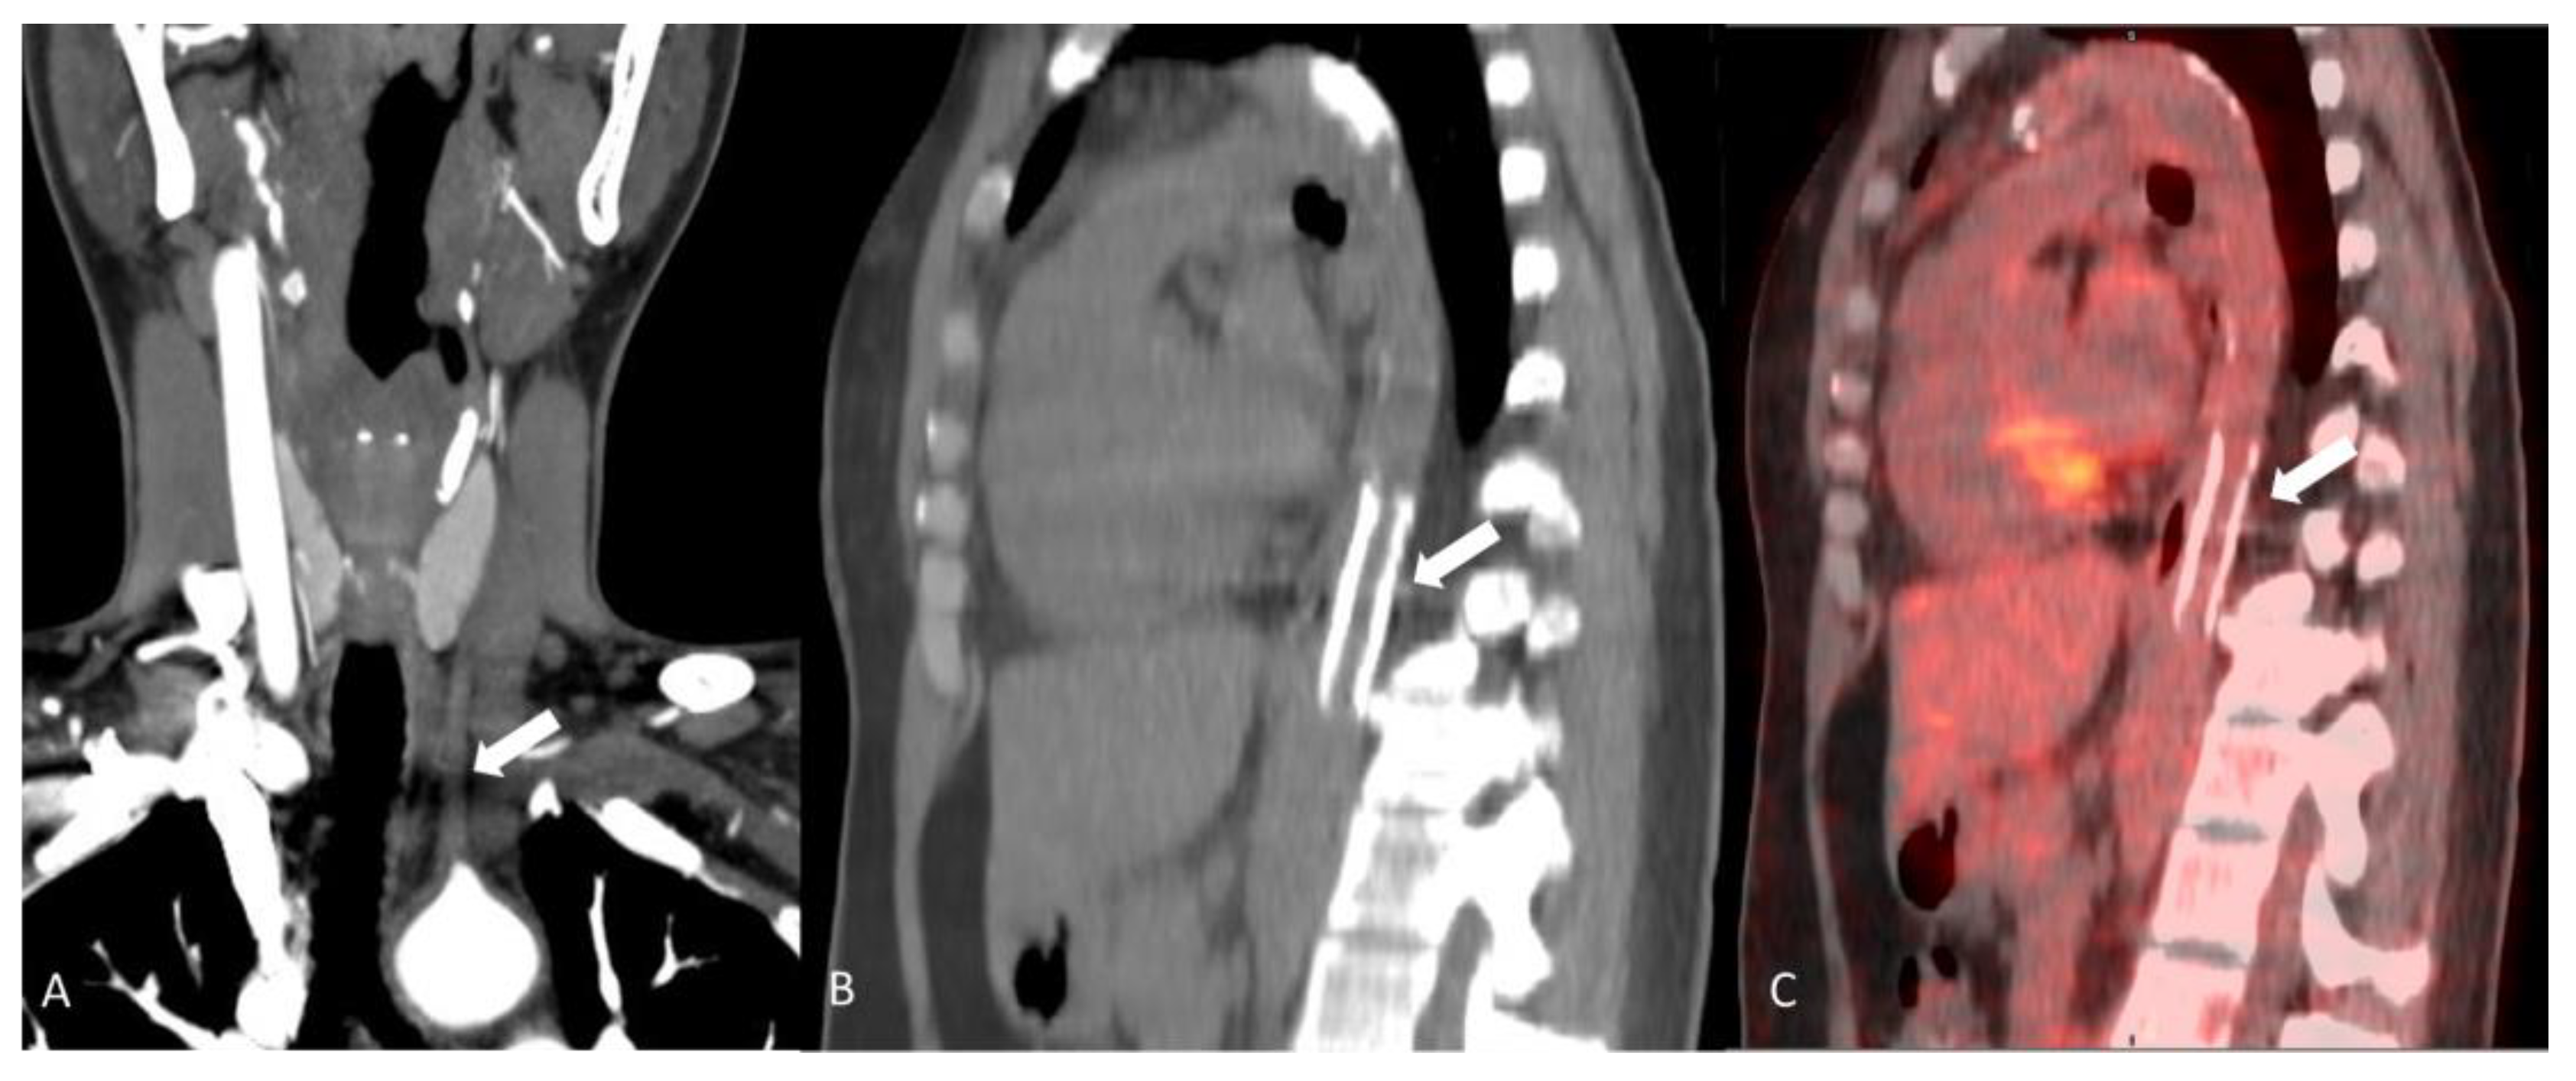

2.4.1. Behçet’s Disease

- Scherrer, M.A.R.; Rocha, V.B.; Garcia, L.C. Behcet’s disease: Review with emphasis on dermatological aspects. An. Bras. Dermatol. 2017, 92, 452–464. [Google Scholar] [CrossRef] [PubMed]

- Giannessi, C.; Smorchkova, O.; Cozzi, D.; Zantonelli, G.; Bertelli, E.; Moroni, C.; Cavigli, E.; Miele, V. Behcet’s Disease: A Radiological Review of Vascular and Parenchymal Pulmonary Involvement. Diagnostics 2022, 12, 2868. [Google Scholar] [CrossRef]

- Seyahi, E. Behcet’s disease: How to diagnose and treat vascular involvement. Best Pract. Res. Clin. Rheumatol. 2016, 30, 279–295. [Google Scholar] [CrossRef]

- Sarica-Kucukoglu, R.; Akdag-Kose, A.; Kayabalı, M.; Yazganoglu, K.D.; Disci, R.; Erzengin, D.; Azizlerli, G. Vascular involvement in Behçet’s disease: A retrospective analysis of 2319 cases. Int. J. Dermatol. 2006, 45, 919–921. [Google Scholar] [CrossRef] [PubMed]